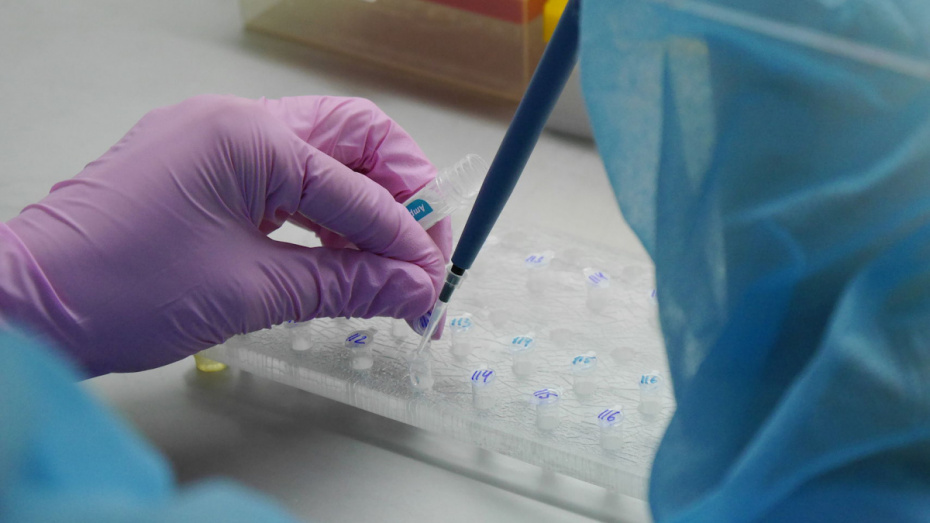

МОЗ: Уперше з початку пандемії було зроблено понад 100 тисяч ПЛР-досліджень за добу